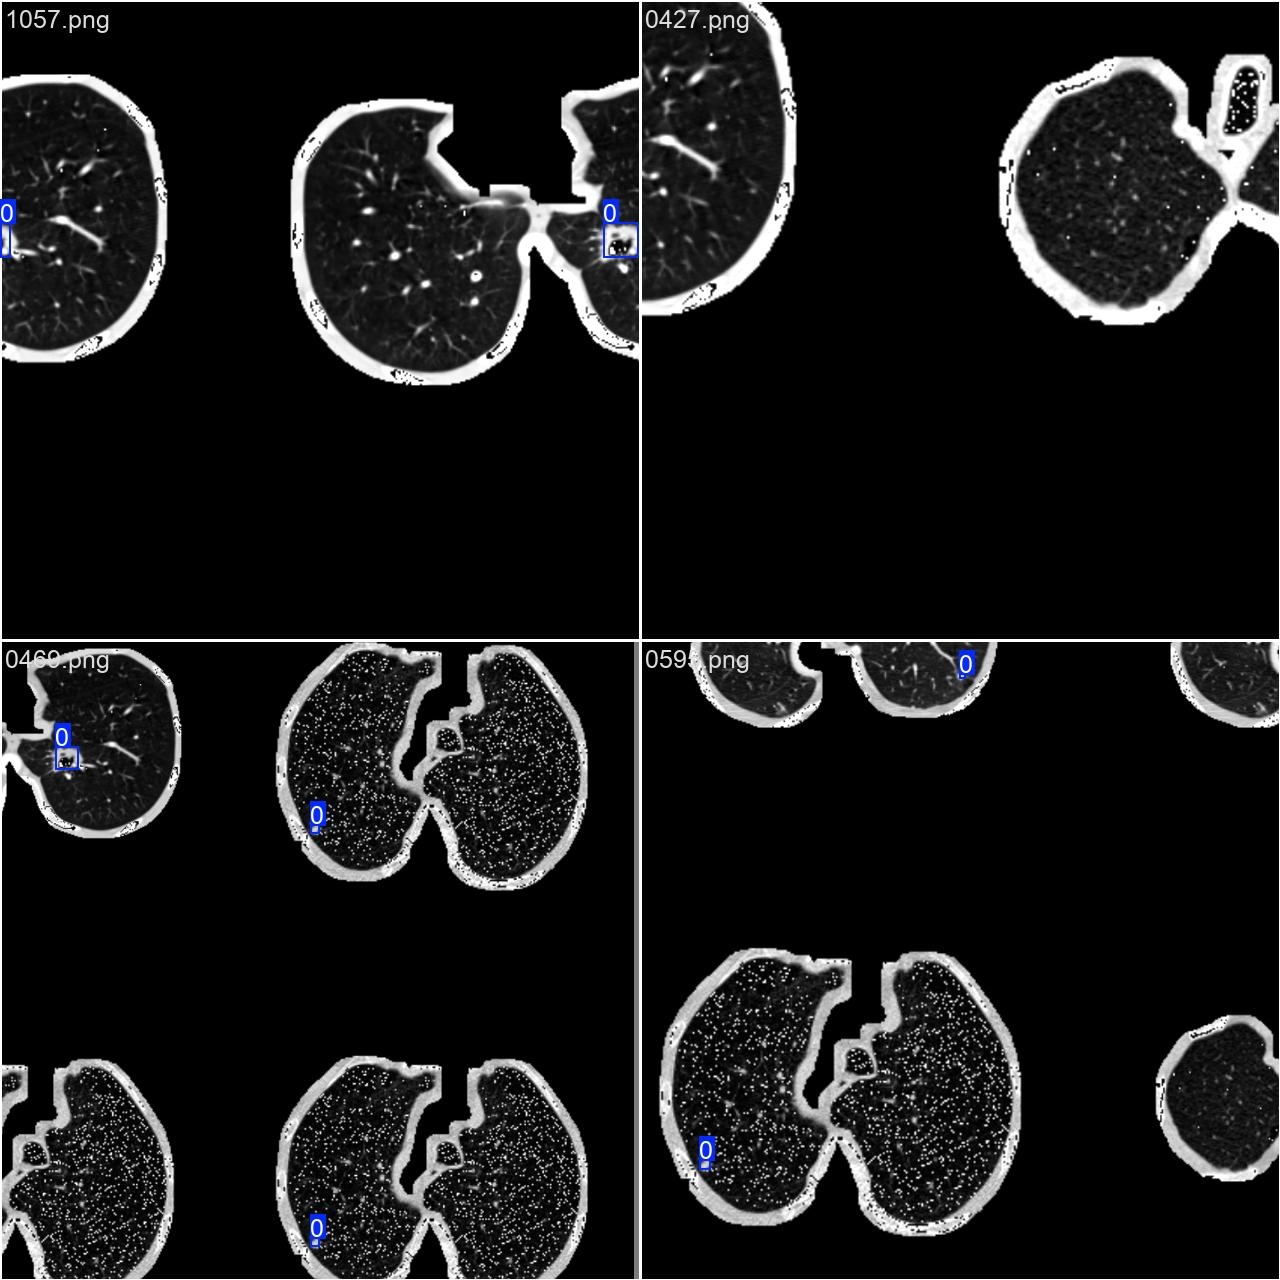

2.数据集准备与训练

本研究采用了包含多种类别的肺结节相关图像的数据集,并借助Labelimg标注工具对每张图像中的目标边界框及其分类信息进行了精确标注操作。随后主要基于YOLOv8n这一模型开展模型训练工作,在完成训练后系统对模型在验证集的表现进行了全面评估与对比分析。具体包括以下几个方面:首先是数据集准备阶段;其次是模型训练过程;最后是模型评估环节。本次研究设定的目标类别为肺结节,在所涉数据集中共有1,186张图片参与其中。其中一些典型实例如图所示

部分标注如下图所示: